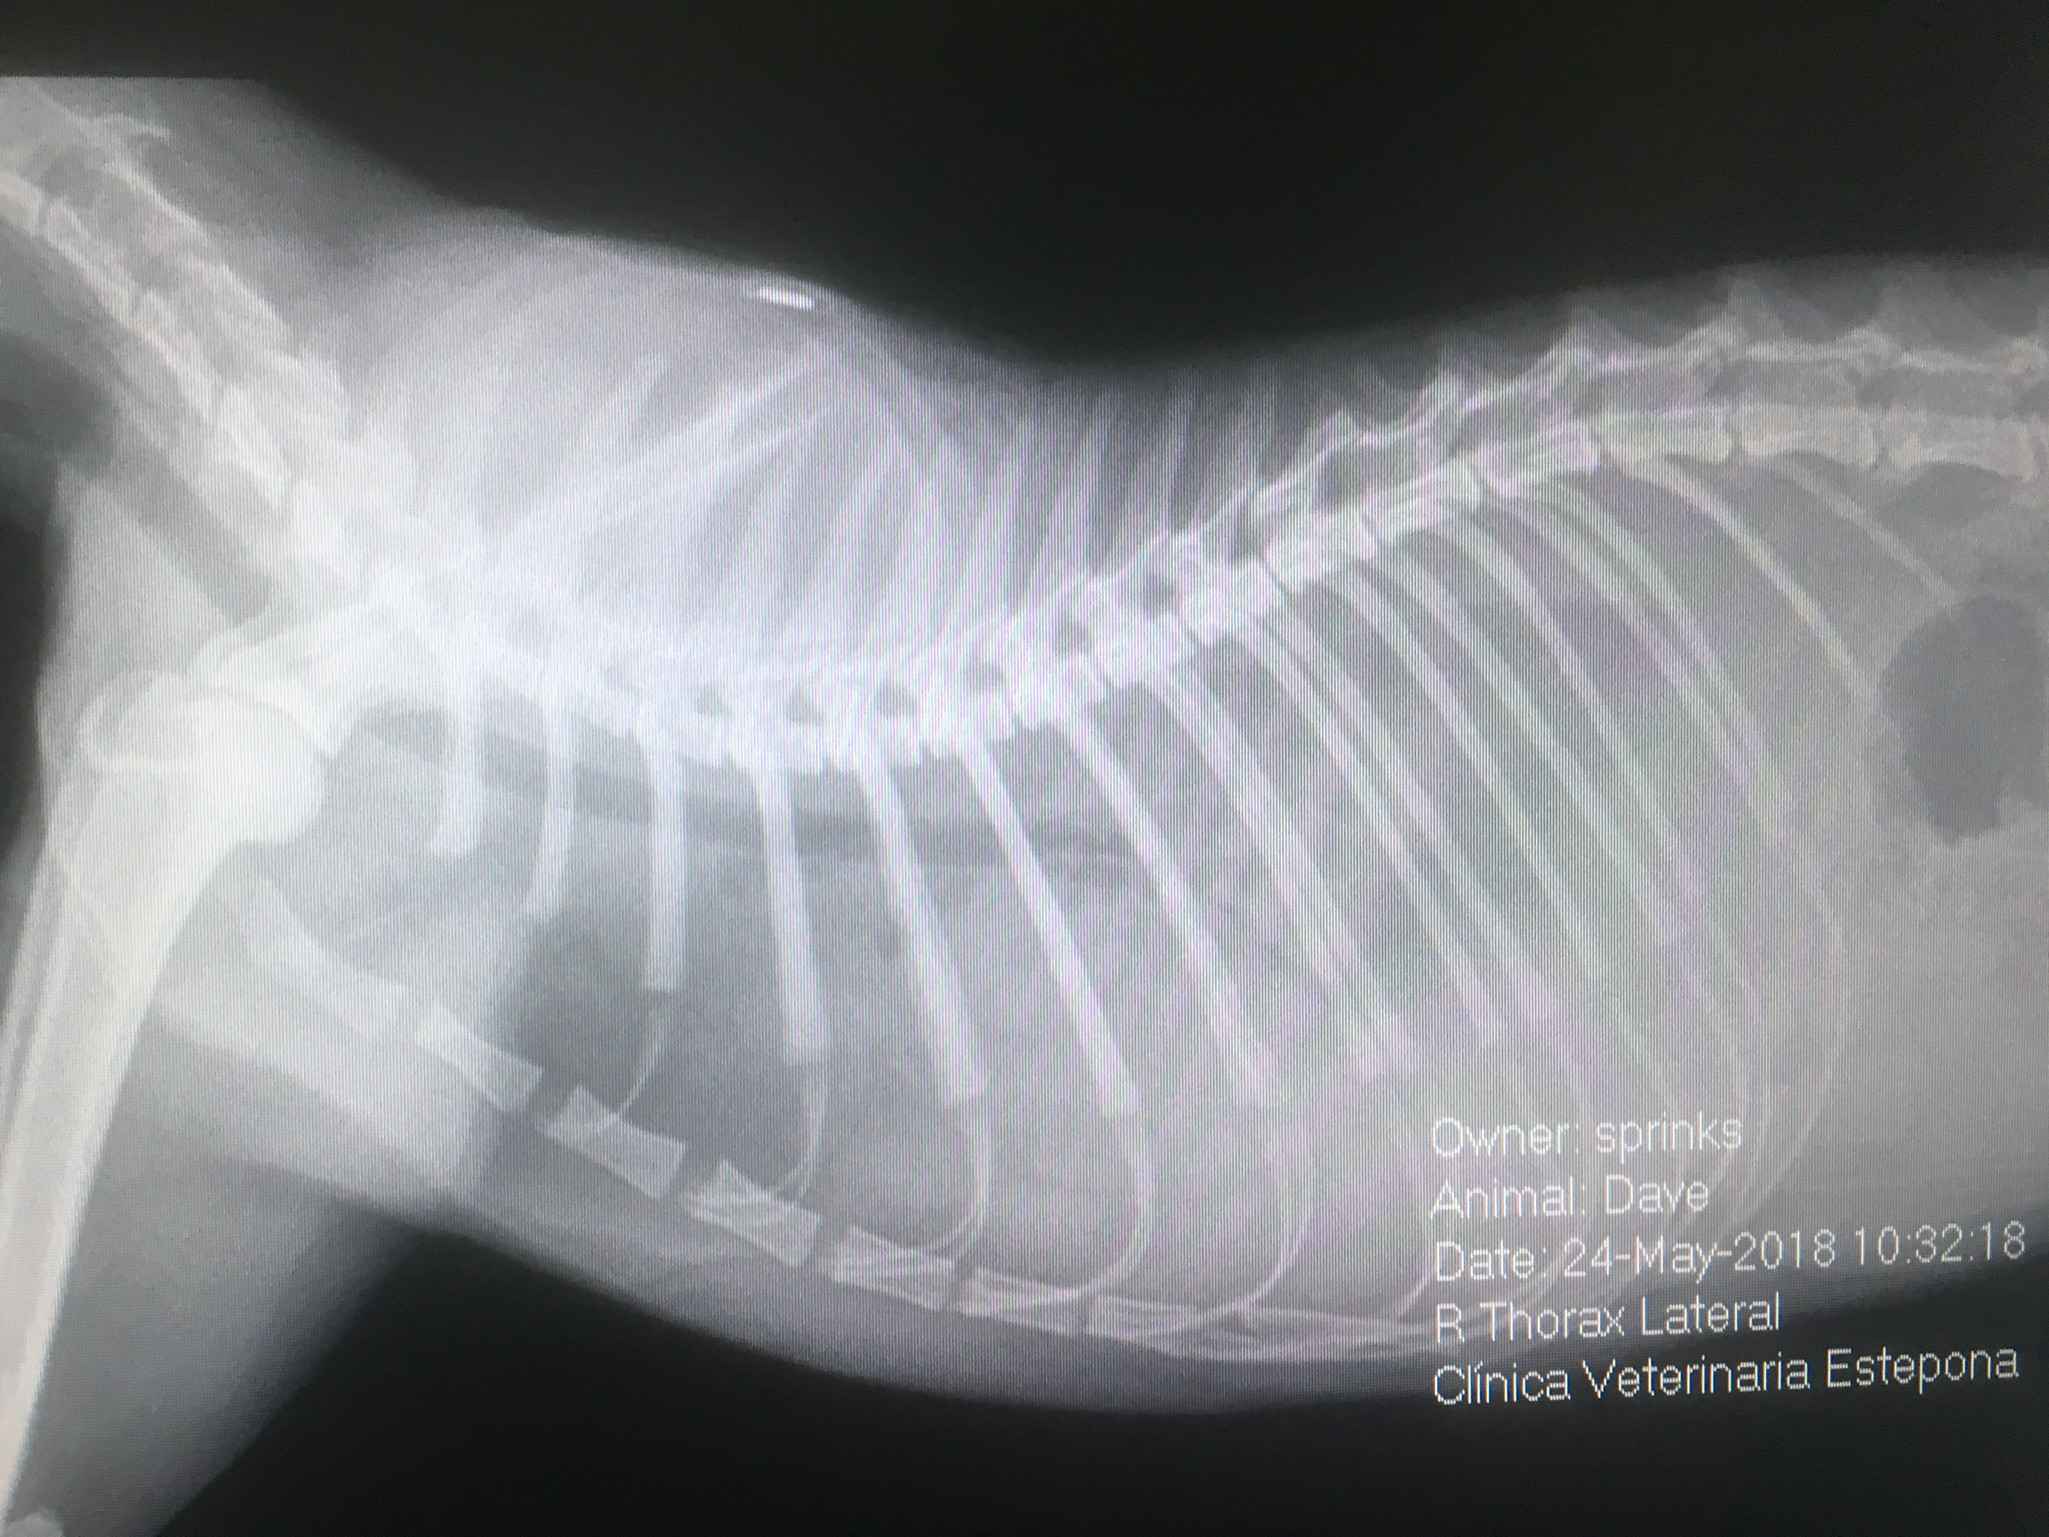

Radiography is an integral part of veterinary medicine, it is not only used for bones, but it can also be used to examine the heart, lungs, and abdominal organs. Advanced procedures such as contrast radiography (cystography for bladder evaluation, myelography for spinal cord evaluation, contrast gastrointestinal study) and positional radiography can be performed.

Digital radiography has revolutionized both human and veterinary medicine because of its convenience and improved detail of soft tissues.

Our certified radiologists combine their veterinary knowledge with state-of-the-art diagnostic equipment to help arrive at a diagnosis and best treatment plan for your pets.